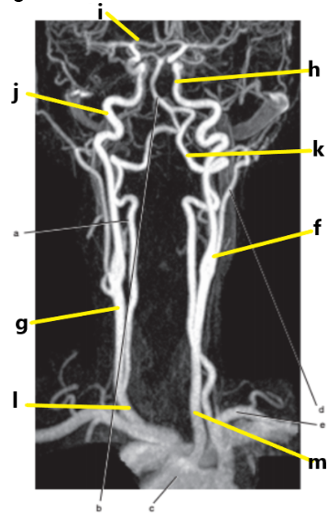

What is letter l ?

Common carotid

What is letter e ?

Subclavian artery

What is letter f ?

Common carotid artery

Anterior cerebral artery

What is letter m ?

What is letter j ?

Internal carotid artery

What is letter g ?

Vertebral artery

Aortic arch

What is letter b ?

What is letter k ?

Carotid sinus/bifurcation